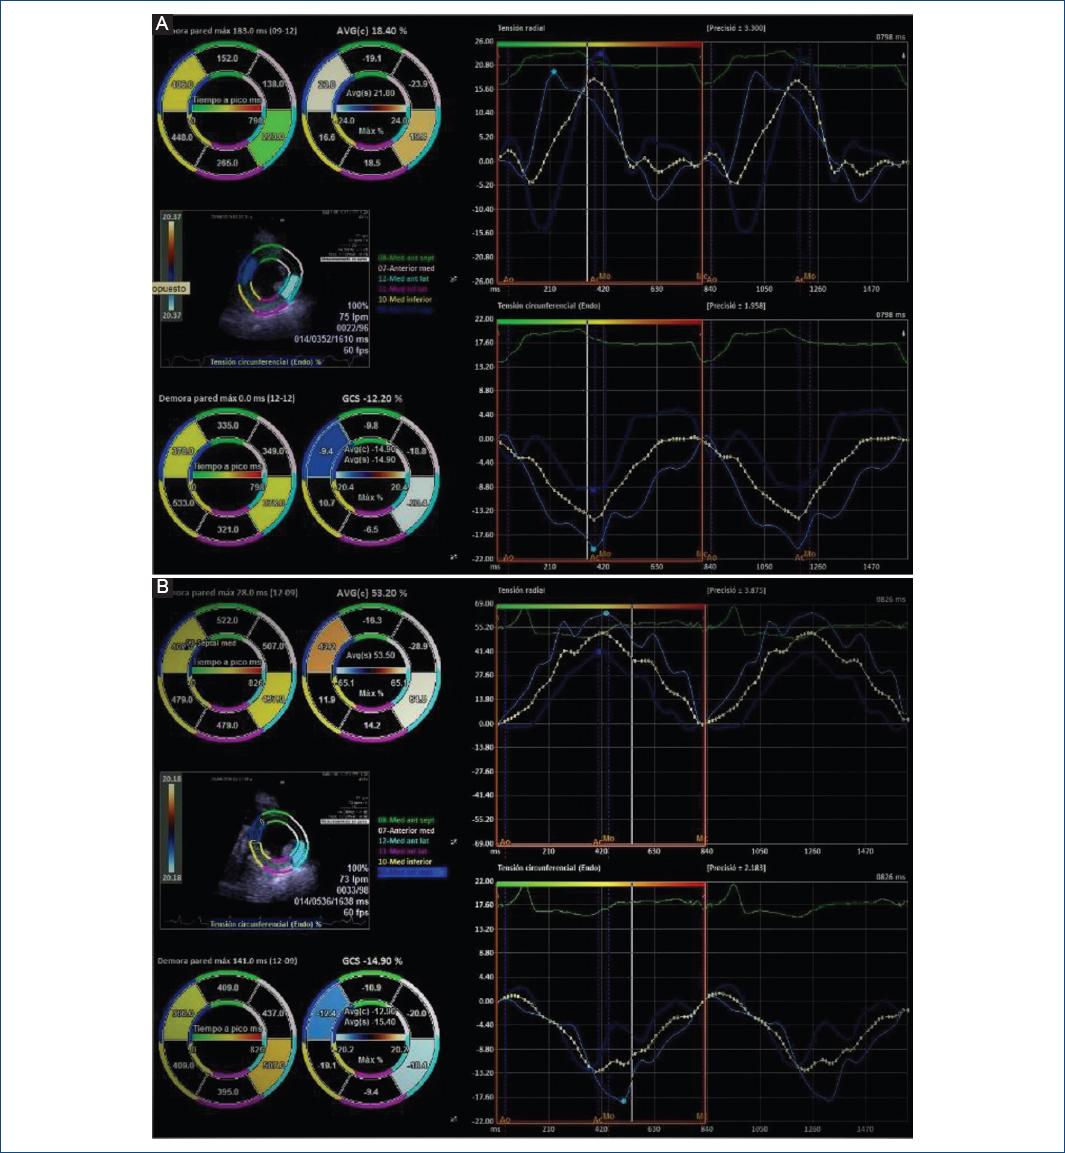

Posterior a 24 horas del procedimiento, se obtuvo ECG con reducción en la duración del QRS (Fig. 2). Se realizó una evaluación ecocardiográfica antes y después de la TRC mediante la técnica de rastreo de puntos (speckle tracking) sin estimulación se observó retraso en la conducción de las paredes anterior y posterior respecto a la pared septal, esto se explica por el BFA (Fig. 3). Posterior a la estimulación hubo mejoría significativa de la asincronía interventricular e intraventricular y la cuantificación de FEVI 3D final con software Syngo en Siemens Accuson S2000 fue del 36.6% (Fig. 4).

Figura 3 Deformación radial y circunferencial mediante técnica de rastreo de marcas (speckle tracking) con análisis por vectores. A: antes de la estimulación hisiana se muestra asincronía intraventricular con un tiempo de retraso en el pico de la deformación radial de 183 ms entre la pared anteroseptal e inferior, con un índice de retraso de deformación del 32%. B: posterior a la estimulación se muestra reducción del tiempo de retraso en el pico de deformación radial de hasta 28 ms y con mejoría también del índice de retraso de la deformación anteroseptal.